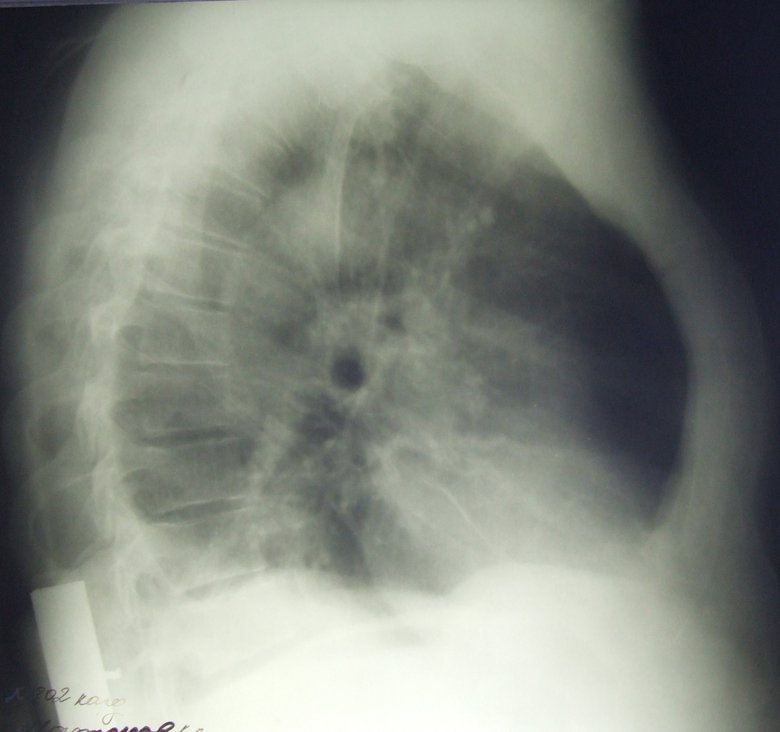

Рак сдавливает бронх и получается гиповентиляция средней доли

Обсуждалось здесь viewtopic.php?f=24&t=2491